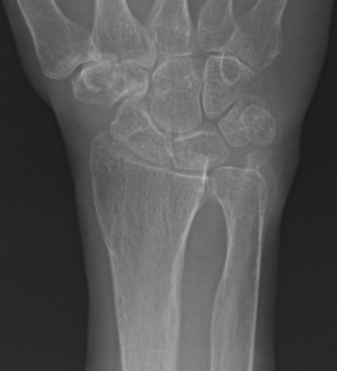

Galeazzi fracture

Galeazzi fracture with DRUJ disruption

Incidence of DRUJ instability after radius ORIF

Rettig et al J Hand Surg Am 2001

- 40 patients with Galeazzi fracture dislocations

- DRUJ instability after radius ORIF

- Type 1: radius fracture < 7.5 cm to articular surface: 55% DRUJ instability

- TYpe II: radius fracture > 7.5 cm to articular surface: 6% DRUJ instability

www.boneschool.com/galeazzi-fracture